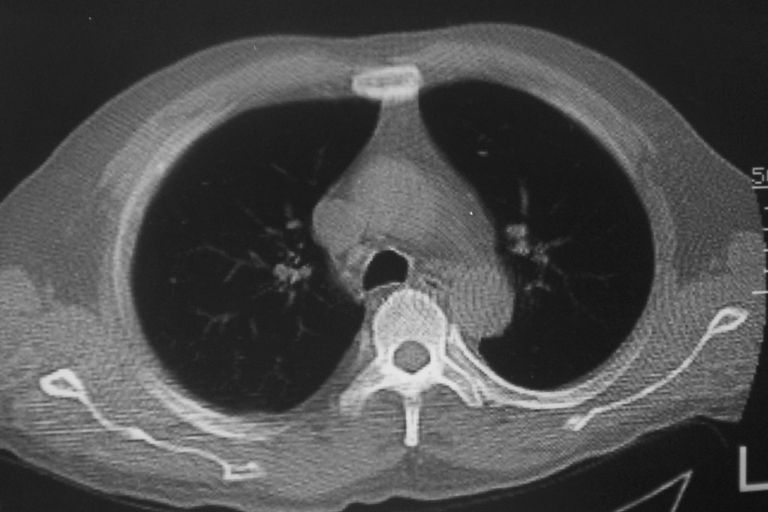

标题: CT10574:男 50岁胸部CT请会诊!

患者 男 50岁 无痛性咯血3天,无其他不适.

1 左肺下叶基底段见两结节软组织密度灶, 肺窗边缘见有毛刺征像, 不能排除占位. 2 建议结合临床治疗一周后ct随访在看其结果.

左下肺基底段两个小结节影,边缘毛糙,建议抗炎治疗后复查。

1 左肺下叶后基底段见结节软组织密度灶,周围见毛刺,建议抗炎后复查,警惕周围型肺癌。

考虑慢性炎症,多发性原发性肺癌待除外.

左下肺结节状软组织密度影,一个边缘有卫星病灶,邻近胸膜增厚.另一个有毛刺.心影周围水样密度影环绕.考虑:

1.肺癌可能.肺tb待排.

2.左侧胸膜增厚.心包积液.